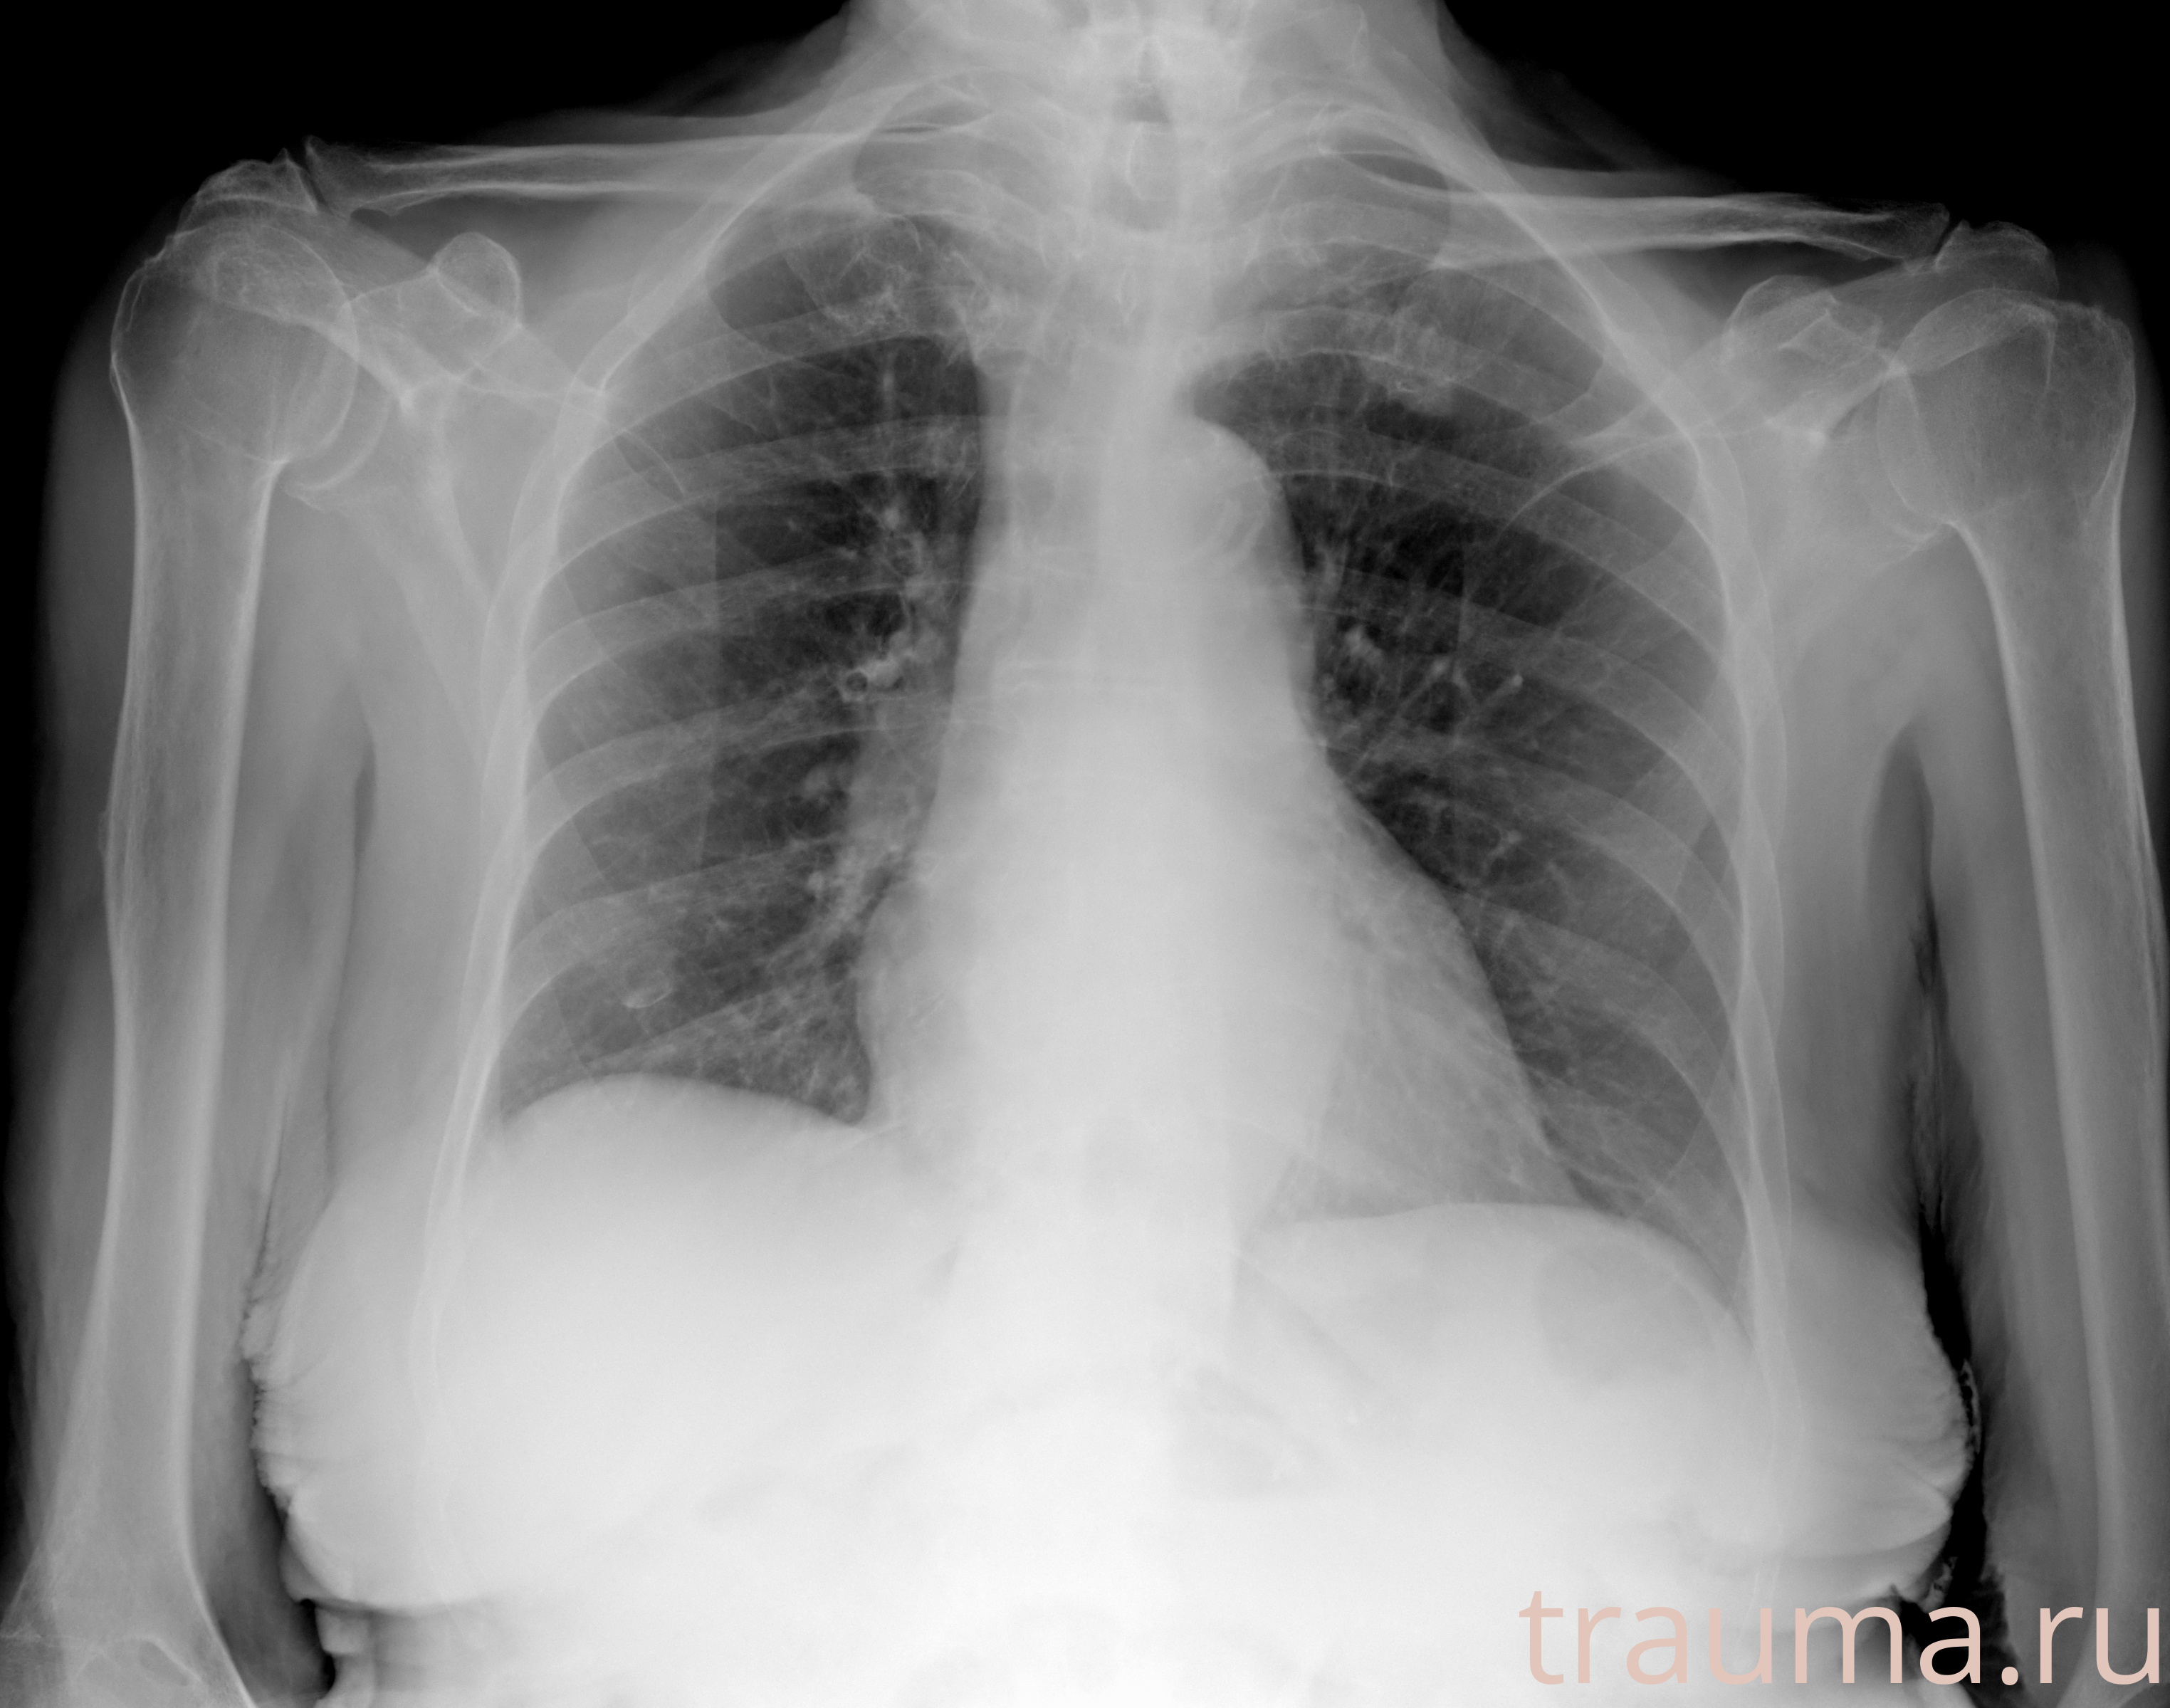

Рентген на дому: по вашему адресу приезжает врач-рентгенолог, травматолог-ортопед с мобильным рентгеновским аппаратом, проводит диагностику травмы или заболевания, делает необходимые рентгенограммы, дает рекомендации по дальнейшему лечению. Получить качественные снимки в домашних условиях возможно благодаря уникальной методике, разработанной МосРентген Центром для института  Склифосовского